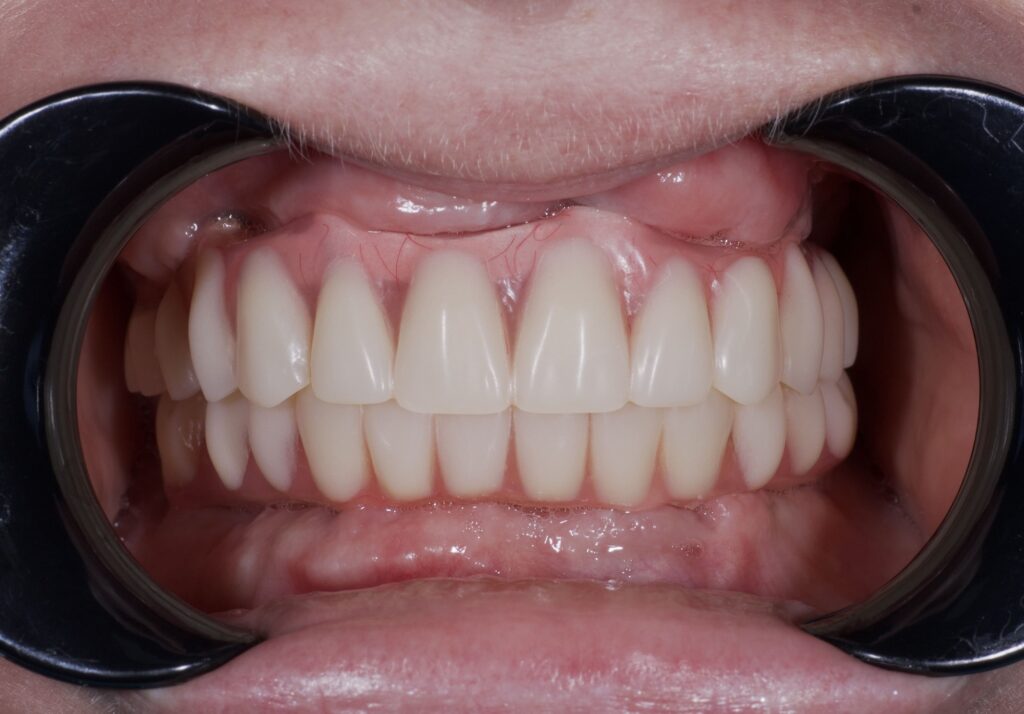

Пациент обратился к нам с целью перепротезирования на постоянные протезы (комплексная имплантация по системе All-on-6 на обе челюсти была проведена в 2024г. специалистами нашей клиники).

По прошествию года было изготовлено 2 постоянных циркониевых протеза на титановой балке.

результат протезирования